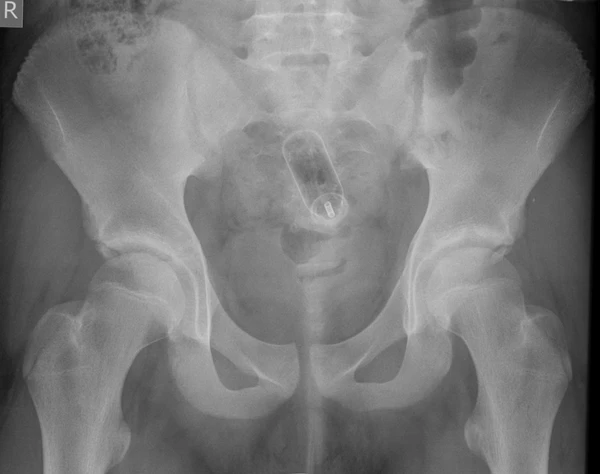

Обычно делают несколько рентгеновских снимков, чтобы точно определить место нахождения инородного тела. Инородные тела из малоконтрастного материала (например, пластика) могут потребовать ультразвукового исследования или компьютерной томографии[23]. Магнитно-резонансная томография противопоказана, особенно если неизвестен материал инородного тела. Инородные тела прямой кишки могут проникать глубоко в толстую кишку, при определённых обстоятельствах вплоть до правого изгиба ободочной кишки[9].